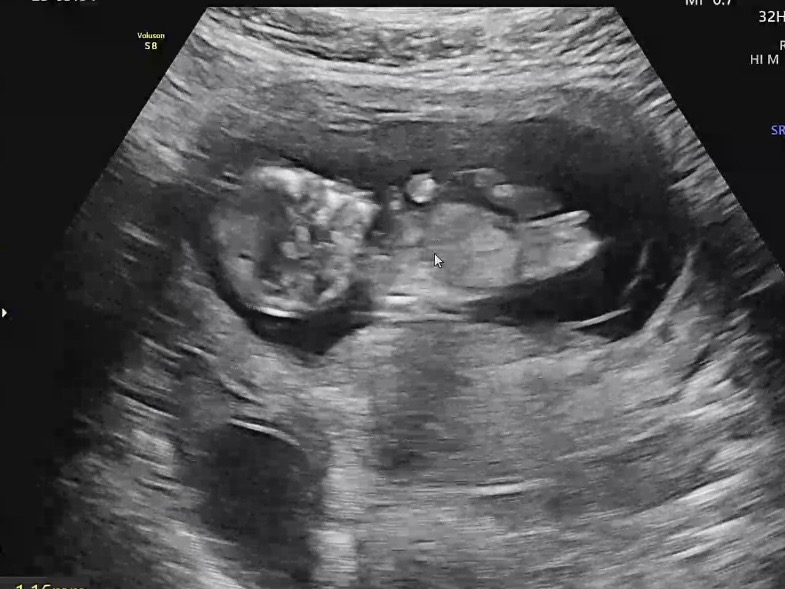

12주 각도법 한 번 봐주세요 ♡

12주 0일 되자마자 궁금해서 다녀왔어요 🤣